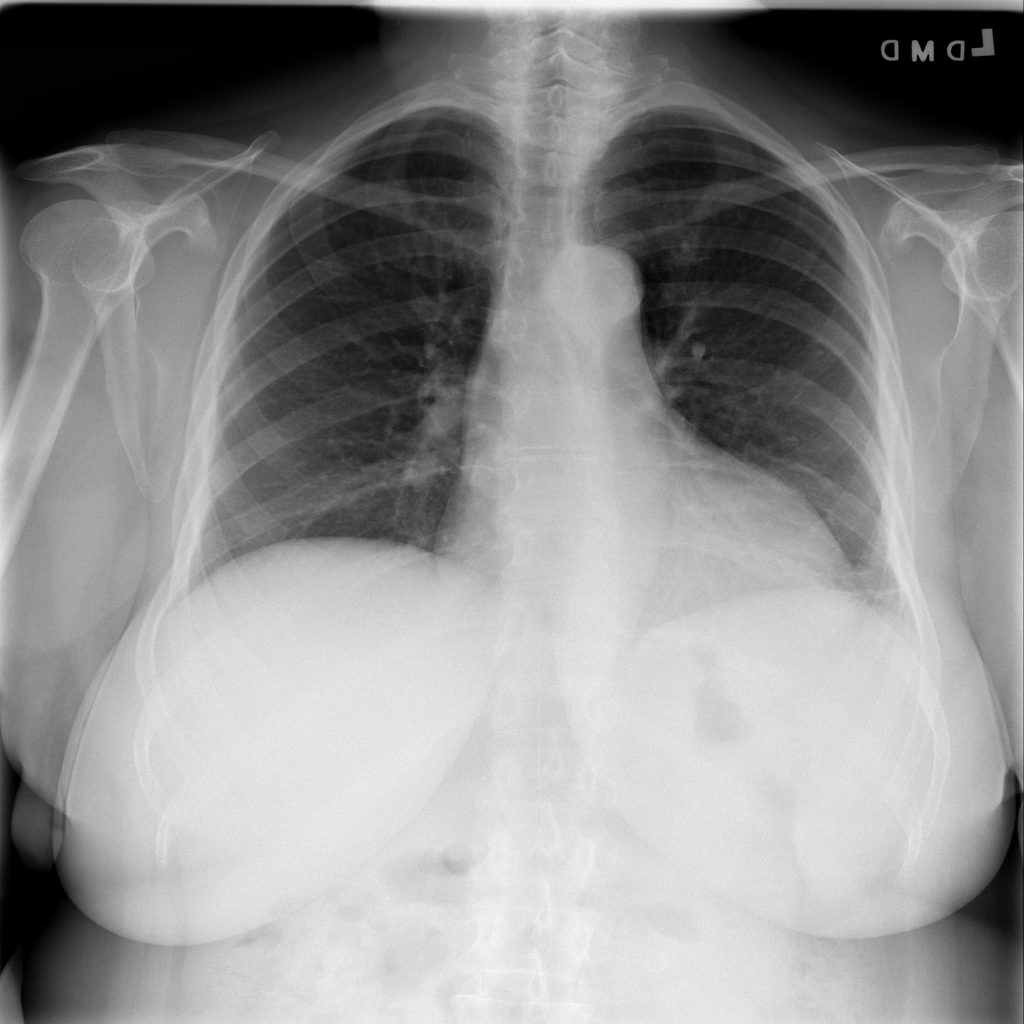

PAT-DB80 · IMG-000Atelectasis

PAT-DB80 · IMG-000

PA